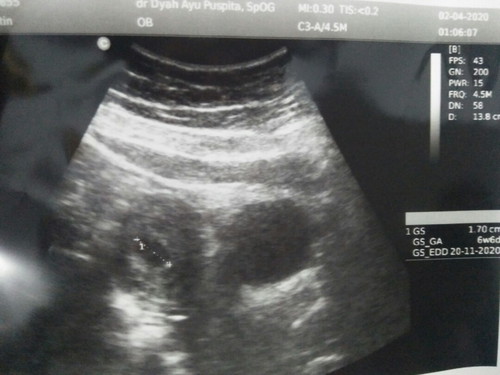

assalamualaikum wr.wb bunda bunda semuanya selamat mlm.. saya td sore baru aja usg. alhamdulillah saya hamil mau 7 minggu. semoga bunda bunda jg sehat dan janin nya juga sehat aminnn

Baca lagiAlhamdulillah sama bunda 7minggu,kemarin usg uda ada detak jatung nya...❤ Sehat terus ya bunda sama debay nya.

7week 3d udah Ada jnin.nya bun sya